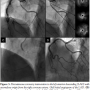

pectoris. His risk factors for coronary artery disease included hyperlipidemia and hypertension. His clinical examination and resting electrocardiogram were unremarkable. An echocardiogram demonstrated normal left ventricular function, with an ejection fraction of 65%. Figure 1 shows the axial view of the multi-detector computed tomography (MDCT) and the schematic representation of the view. These studies showed an abnormal course of the coronary arteries.

Coronary angiography was performed through the right radial artery. The angiogram revealed findings similar to the MDCT. First, the RCA could be cannulated with a 5 Fr Heartrail™ Ikari Left 4.0 curve (Terumo Corporation, Tokyo, Japan) (Figure 3A). After the 0.014˝ Asahi Sion™ guidewire (Asahi Intecc, Nagoya, Japan) was inserted into the RCA, the other 0.014˝ Runthrough™ NS guidewire (Terumo Corporation) was inserted into the anomalous origin of the LAD with pulling up and rotating counter-clockwise the guiding catheter a little.

The stenosis was evaluated by intravascular ultrasound (IVUS) ViewIT® (Terumo Corporation) (Figure 3B). The IVUS showed a focal eccentric plaque with attenuation in the LAD lesions. A 2.5 x 12 mm Xience V™ stent (Abbott Vascular, Santa Clara, California) was then implanted at 12 atm (Figures 3C and 3D). Then, the same guiding catheter could cannulate into the LCX that arose from the separate ostium in the posterior right coronary cusp (Figure 4A). The 0.014˝ Runthrough™ NS guidewire was inserted into the LCX, and IVUS showed a focal concentric fibrous plaque with negative remodeling in the LCX lesions (Figure 4B). A 2.75 x 15 mm Xience V stent was implanted at 12 atm (Figures 4C and 4D). The final angiogram showed optimal angiographic results in both lesions. The procedure time was 45 minutes, with 19.5 minutes of fluoroscopy and 125 ml of contrast used. The patient had no complications during hospitalization and was discharged the next morning.